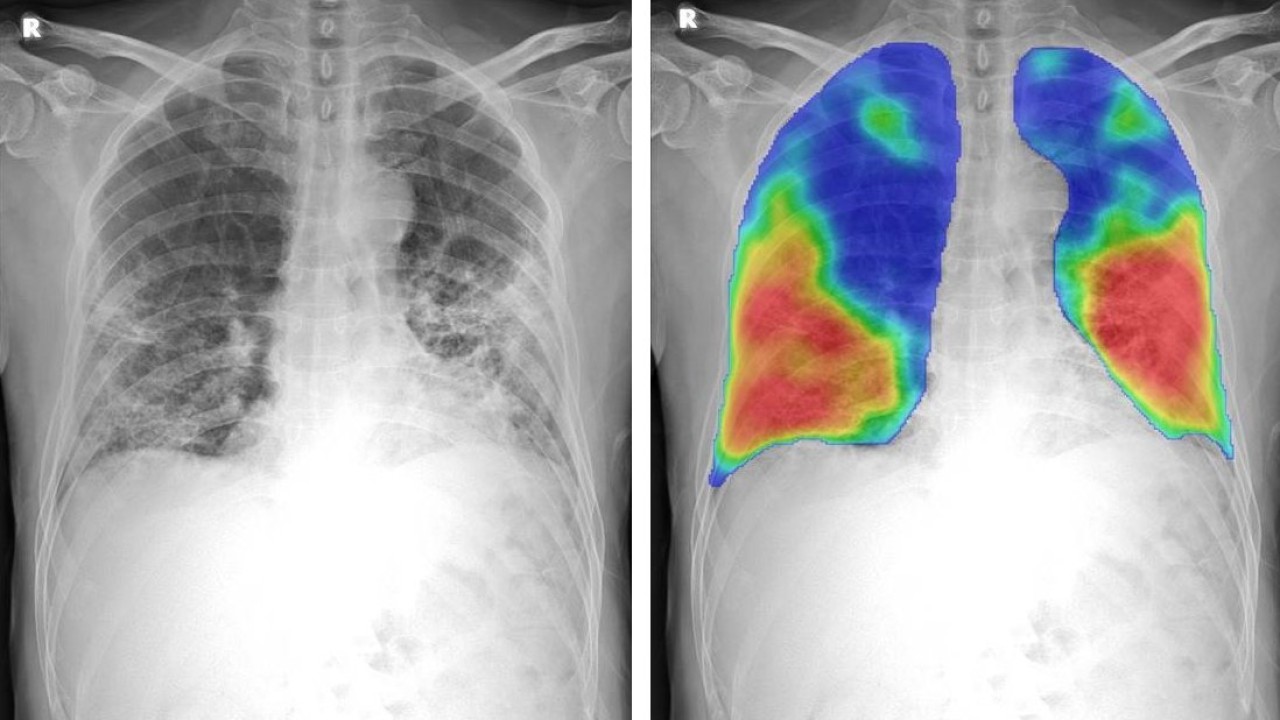

Ancak bu durum yakında tamamen değişebilir. Yeni bir çalışmada, Iowa Üniversitesi'ndeki bilim insanları tarafından karşılaştırmalı öğrenme modeli adı verilen yeni bir saptama projesi geliştirildi. Bu yeni model, 3D BT görüntülerinden oluşturulan kompozit 2D görüntüleri kullanarak COVID-19 hastalarında riskli akciğer fonksiyonunun nasıl tespit edileceğini gösterir. Transfer öğrenme adı verilen başka bir teknik ise daha sonra bir BT taramasından akciğer diyagnostik bilgilerini bir göğüs röntgenine aktarır. Böylece göğüs röntgeni ekipmanının, sanki bu hastalar bir BT taraması kullanmış gibi anormallikleri tespit etmesine olanak tanır.

Frontiers in Physiology dergisinde yakın zamanda yayınlanan çalışmada araştırmacılar, karşılaştırmalı öğrenme modellerinin, COVID-19 hastalarında akciğer fonksiyonunun erken bir aşaması olan küçük hava yolları hastalığını tespit etmek için nasıl uygulanabileceğini gösterdiler. COVID-19 hastalarının modelleri, küçük hava yolları hastalığı olanları daha ileri solunum sorunları olanlardan ayırarak, tehlikeye giren akciğer fonksiyonunun ciddiyetini ayırt edebiliyordu.

Araştırmacılar modellemelerini, COVID ile enfekte olan ve solunum sorunları nedeniyle teşhis için hastanelere giden 100 kişinin BT taramalarına dayandırdı.

Araştırmacı ekip, BT akciğer taramalarında hasta nefes aldığında ve hasta nefes verdiğinde olmak üzere iki aralıkta veri noktaları topladı. Araştırmacılar, karşılaştırmalı öğrenme modelini oluştururken sonuçlarını virüs bulaşmamış bir kontrol grubuyla karşılaştırdı.